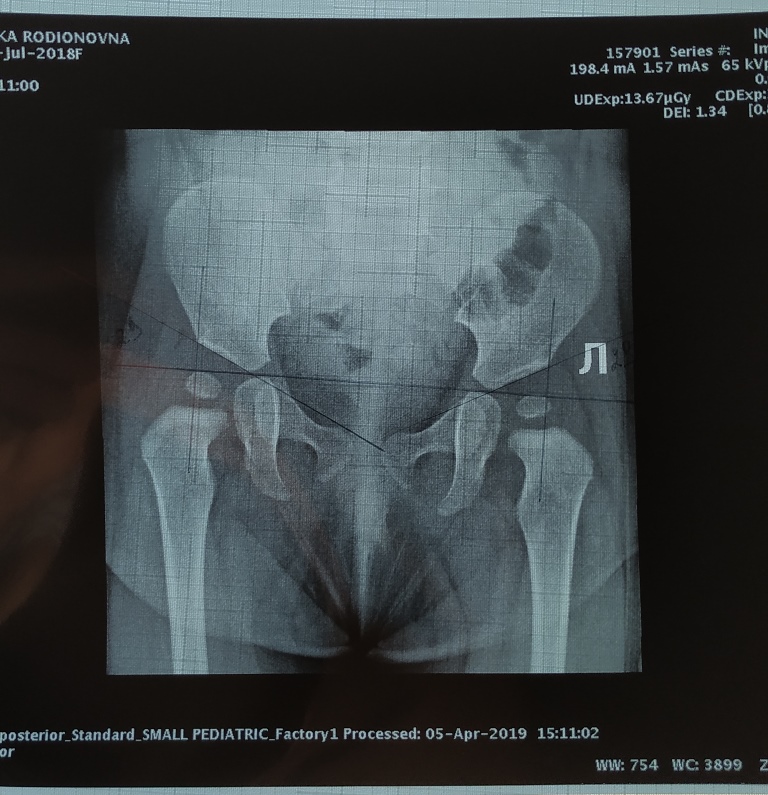

Но иногда картины УЗИ недостаточно, поэтому используют рентгенологический метод. Так как исследование необходимо детям, а рентген сопряжен с лучевой нагрузкой, такую диагностику стараются использовать реже. Но ее информативность невозможно переоценить. На рентгеновских снимках можно увидеть ясную картину взаимодействия компонентов сустава друг с другом.

Клинический осмотр малыша проводят после кормления, в теплом помещении, в спокойной тихой обстановке. Для уточнения диагноза применяют такие методики, как рентгенография и ультрасонография. У детей раннего возраста значительная часть сустава образована хрящами, которые не отображаются на рентгенограммах, поэтому до достижения 2-3-месячного возраста этот метод не используется, а в последующем при чтении снимков применяются специальные схемы. Ультразвуковая диагностика является хорошей альтернативой рентгенологического исследования у детей первых месяцев жизни. Эта методика практически безопасна и достаточно информативна.

Диагностика: исследования изображений

Ультрасонография — это рекомендуемый метод визуализации у детей младше 4 месяцев, поскольку бедро ребенка преимущественно хрящевое, что не позволяет получить четкую рентгенографическую визуализацию.Ультрасонография позволяет визуализировать расположение головки бедренной кости относительно вертлужной впадины и конкретные анатомические параметры, такие как глубина вертлужной впадины и наклон крыши вертлужной впадины. Основные ультразвуковые измерения показаны на рис. 3. Визуализация может быть статической или динамической. В статическом исследовании исследователи изучают анатомию сустава (то есть форму и соотношение между головкой бедренной кости, вертлужной впадиной и верхней губой). Во время динамического ультразвукового исследования стабильность тазобедренного сустава оценивается путем выполнения манипулятивных маневров напряжения под прямым визуальным наблюдением.Ультрасонография может использоваться как для начального скрининга младенцев на ДДГ, так и для наблюдения за пациентами с ДДГ, проходящими активное лечение. Ядро окостенения головки бедренной кости становится видимым рентгенологически в возрасте от 4 до 6 месяцев. Следовательно, рентгенограммы не рекомендуются для оценки DDH до 4-месячного возраста. После возраста примерно 6 месяцев рентгенограммы являются предпочтительным методом оценки и мониторинга DDH после более надежного появления оссификации головки бедренной кости. Важно отметить, что пораженное бедро при DDH часто демонстрирует отсроченную рентгенографическую картину центра окостенения головки бедренной кости.Основные рентгенографические измерения и углы изображены на рис. 4.

РИСУНОК 3Корональные ультразвуковые изображения бедра с дисплазией в 2 месяца. Ключевые ультразвуковые измерения включают α (который образован костной подвздошной костью и костной крышей вертлужной впадины), угол β (который образован костной подвздошной костью и лабральным фиброзным хрящом) и процент головки бедренной кости, покрытой костная крыша вертлужной впадины. Угол α имеет большее клиническое значение, чем угол β. На этом изображении (1) головка бедренной кости не входит глубоко в гнездо, <50% головки бедренной кости покрывается вертлужной впадиной, и (2) вертлужная впадина неглубокая (нормальный α> 60 °).